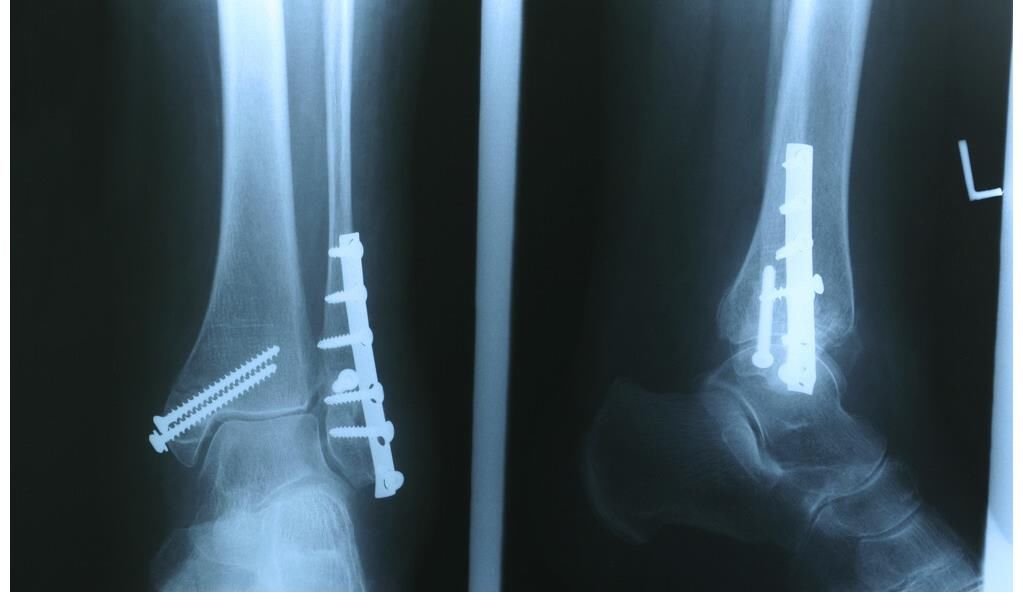

3.骨折

是退行性骨质疏松症最常见和最严重的并发症。

(3)骨的脆性增高、骨折危险性增加

骨支撑人体及抵抗外力的功能减弱,脆性增加,变得容易骨折。当骨密度严重降低时,连咳嗽、开窗、弯腰端水这样的小动作也可能导致骨折。与骨质疏松密切相关的骨折,即非暴力下的骨折,通常称为骨质疏松性骨折。